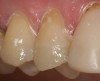

Magne23 described the technique of immediate dentin sealing with the use of a three-step dentin bonding adhesive system. The author has made modifications to this technique as follows. After the tooth has been prepared and isolated, the enamel and dentin are etched with 35% phosphoric acid for 30 and 15 seconds, respectively (Figure 1). Both surfaces are then thoroughly rinsed with water and gently air-dried for 5 seconds. A desensitizer is then vigorously applied to the dentin surface with a microbrush applicator for 30 seconds (Figure 2). To remove excess desensitizing agent from the dentin surface, the microbrush applicator is dried with a gauze pad and then brought back to the wet dentin surface to absorb the excess desensitizer. This step is repeated twice and provides a sufficient wet surface to the dentin. Next, a primer is applied to the enamel and dentin with a microbrush applicator using a light scrubbing motion for 30 seconds (Figure 3). Using light air pressure, the excess primer is air-thinned but still leaves a slightly moist surface. In other words, the surfaces are not desiccated but are left moist. An adhesive is then applied to the enamel and dentin surfaces using a scrubbing motion with a microbrush applicator (Figure 4). The adhesive should be left in contact with the tooth for 30 seconds and then air-thinned. A second coat of adhesive is then applied for the same length of time before it is air-thinned. The adhesive is then light-polymerized for 5 seconds. This step is necessary to fix the adhesive in place before applying a water-soluble glycerin gel. After the initial light polymerization, the gel is applied with a syringe over the adhesive-covered area to block out the oxygen (Figure 5). This step is necessary to eliminate the formation of an oxygen-inhibited layer on the adhesive surface. The presence of the oxygen-inhibited layer can interfere with the surface polymerization of polyvinyl and especially polyether impression material.24 The polymerization of the adhesive is then resumed (Figure 6) for 30 seconds. The glycerin gel is washed away and the tooth is air-dried. A scaling instrument is then used to remove any adhesive flash remaining beyond the margin. After the impression, the temporary restoration can be fabricated and placed with non-eugenol provisional cement.

Figure 1  After the tooth was prepared and isolated, the enamel and dentin were etched with 35% phosphoric acid for 30 and 15 seconds, respectively.

Figure 1